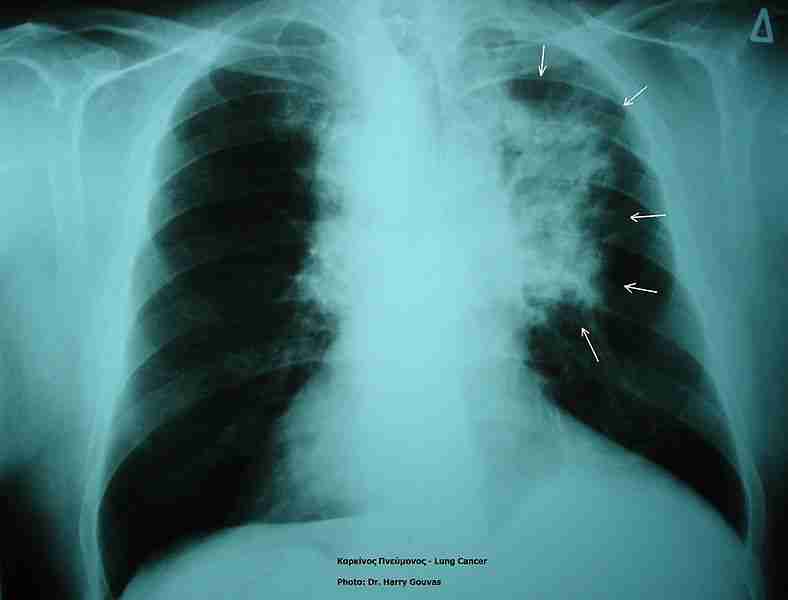

Called CIMAvax-EGF, the treatment is an immunotherapy developed by Havana’s Center of Molecular Immunology. The trial will involve 60 to 90 patients and is expected to begin next month.